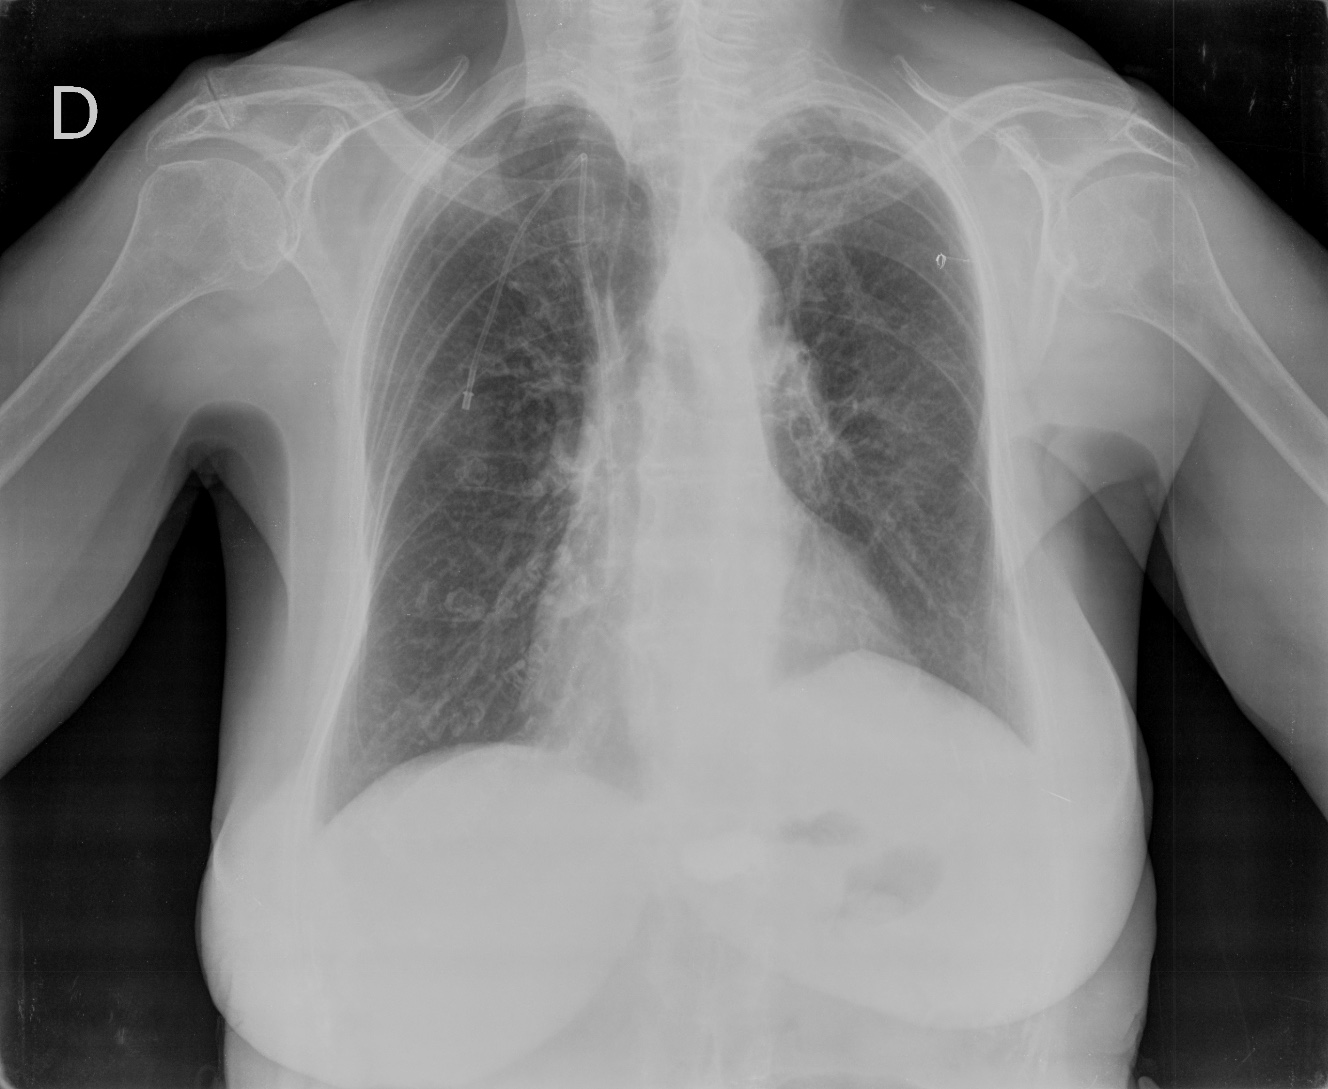

CASO: Operada de esofaguectomia y reconstrucción con coloplastia hace 3 meses. Sintomas de neumonía.

Hallazgos:

- De inicio llama la atención una densidad practicamente total del todo el hemitórax izquierdo, lo cual podría hacernos pensar que estamos ante una posible neumonía.

- Sin embargo el tórax está no está bien centrado, observar como la clavícula izquierda se encuentra casi en la mitad del pulmón, por tanto lo que vemos blanco es el mediastino ya que el tórax está rotado.

CENTRAJE:

El correcto centraje se determina comprobando que las extremidades internas de ambas clavículas equidistan de las apófisis espinosas vertebrales.

Mismo paciente, al cual esta vez se le ha tomado una radiografía en PA y en sedestación. Observar como las clavículas están equidistantes a las apófisis espinosas y como ha desaparecido el velamiento del pulmón izquierdo.

Por otra parte, paciente presenta una cardiomegalia y un discreto ensanchamiento del mediastino es probable relación con cambios postquirúrgicos.